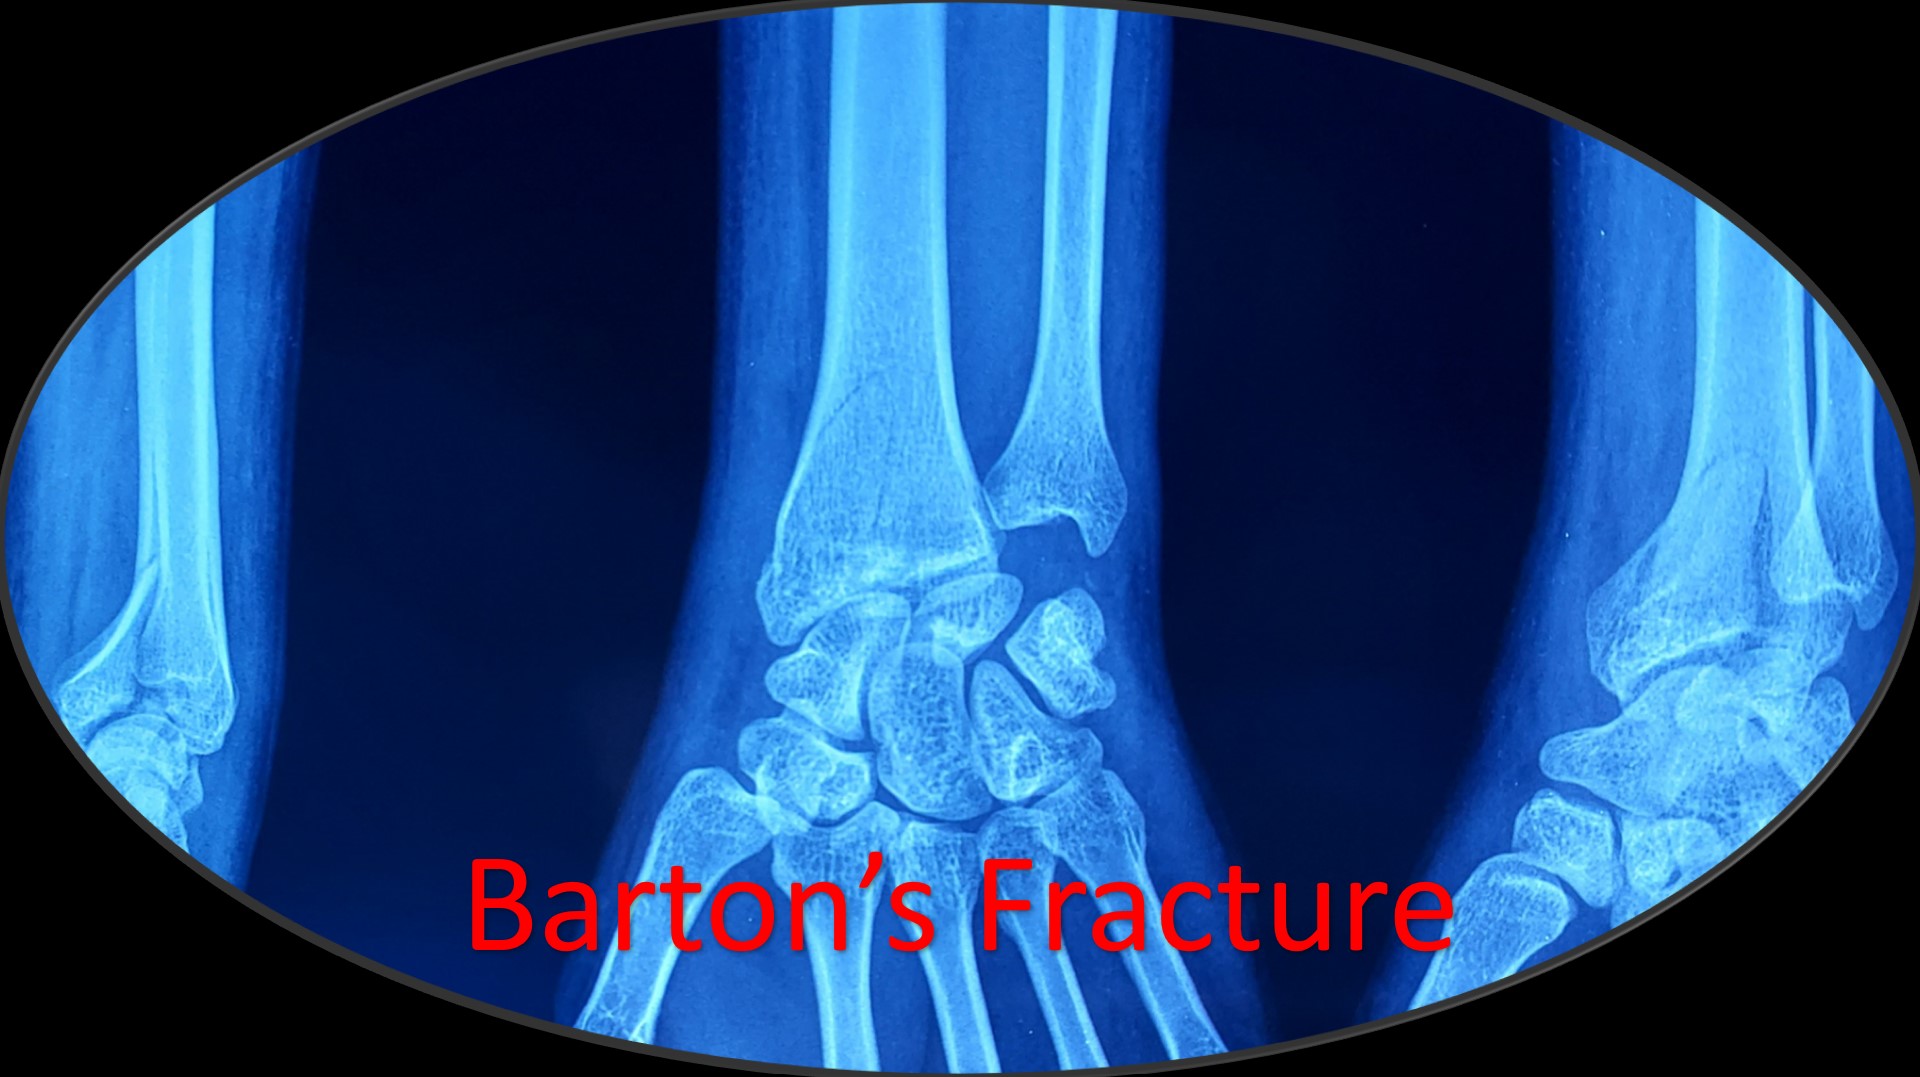

• It can be applied to any intraarticular fractures, distal end radius, elbow, ankle and foot.

·        A Novel Method of Closed Reduction and Percutaneous Pinning with Six K-wires for Intra-articular Fractures of the Distal Radius. Anilkumar Vidyadharan, MBBS, D. Ortho, JAAOS Global Research & Reviews (June 2020-volume-4-issue 6)